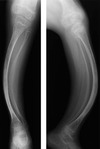

Osteogénesis imperfecta

- Osteopenia difusa

- Adelgazamiento cortical

- Arqueamiento y estrechamiento de tibia y peroné

Osteomalacia por raquitismo vit. D resistente: Tibia

- Osteopenia

- Múltiples fracturas/pseudofracturas

- Incurvación ósea

Osteomalacia por raquitismo vit. D resistente: Fémur

- Discreta osteopenia

- Incurvación ósea

- Pseudofractura

- Genu varo